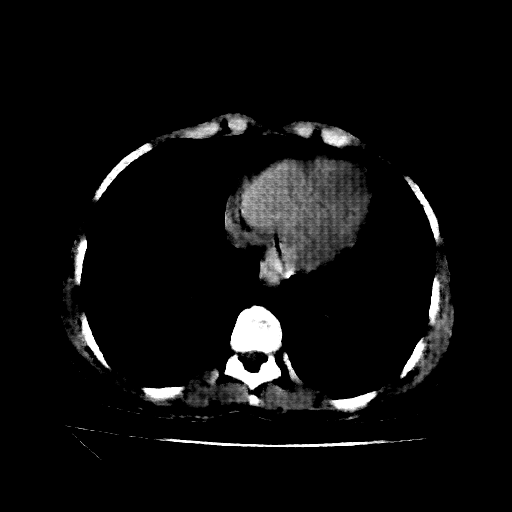

Original NATIVE CT scan (input)

Full window (WL 1023.5, WW 4095 β†’ Low βˆ’1024, High +3071)

Actual HU range: [-160.0, 240.0]

Lung window (WL -600, WW 1500 β†’ Low βˆ’1350, High +150)

Actual HU range: [-160.0, 150.0]

Mediastinum window (WL 40, WW 400 β†’ Low βˆ’160, High +240)